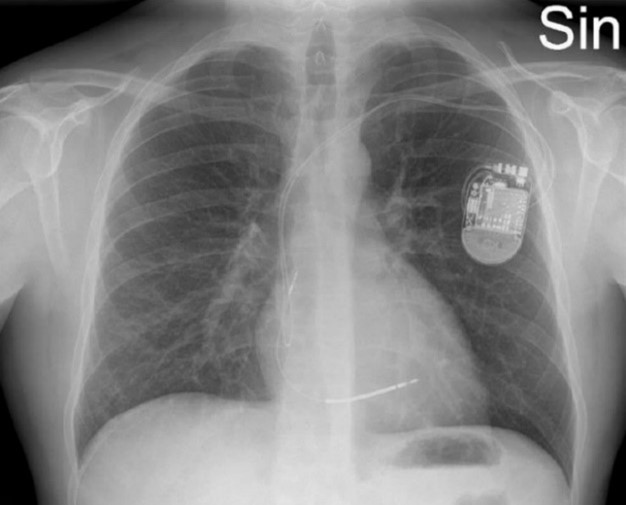

För närmare kartläggning av inflammationens utbredning utförs PET-DT

Tolka bilderna. Vilka anatomiska strukturer ”lyser” (inflammation/ämnesomsättning)?

- Ökat FDG-upptag i

- Hjärta ①

- Hiluslymfkörtlar ②

- Mjälte ③

- Isotopen utsöndras via njurar

För närmare kartläggning av inflammationens utbredning utförs PET-DT

- Ökat FDG-upptag i

- Hjärta ①

- Hiluslymfkörtlar ②

- Mjälte ③